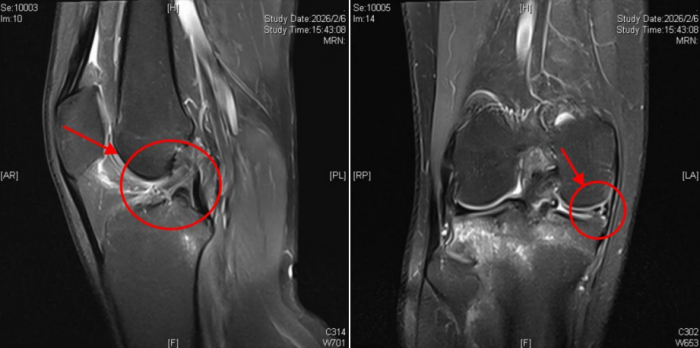

核磁检查提示右膝关节前交叉韧带断裂合并半月板破裂

3月1日,他来到长沙市中心医院运动医学科余敏主任门诊,经详细查体并结合磁共振检查,确诊为前交叉韧带断裂合并半月板撕裂。为了恢复关节的稳定以及防止继发软骨损伤,余敏主任为其实施关节镜下前交叉韧带重建联合半月板缝合修复术,术后患者恢复顺利,对治疗效果十分满意。